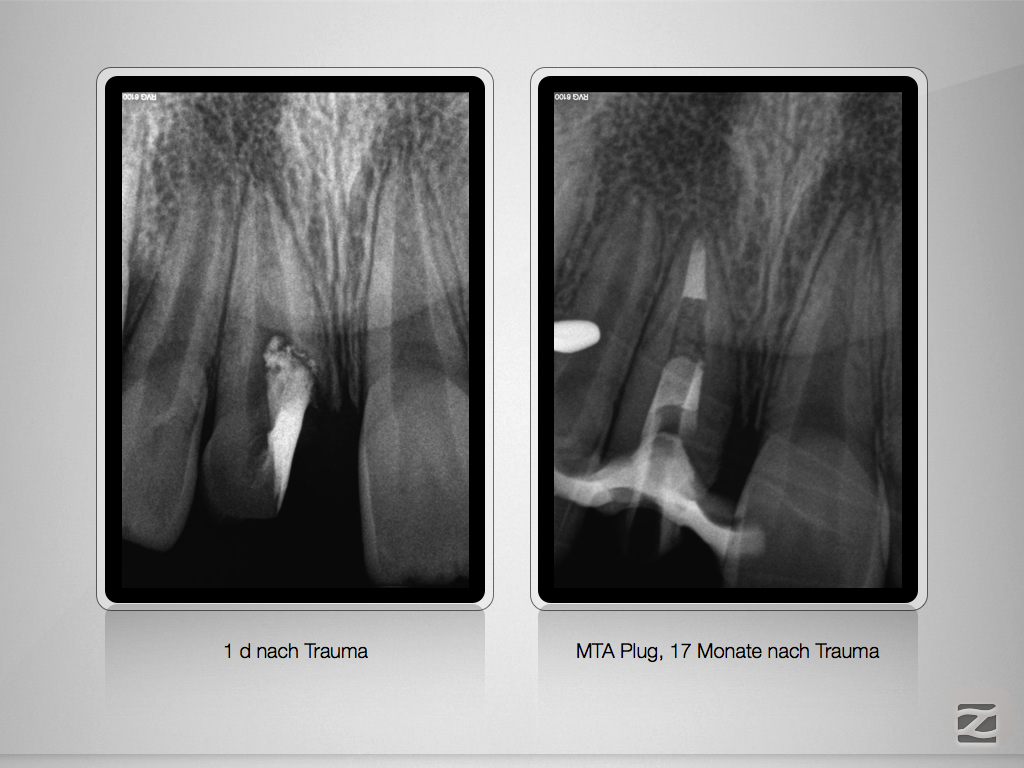

Komplizierte Kronen-Wurzelfraktur